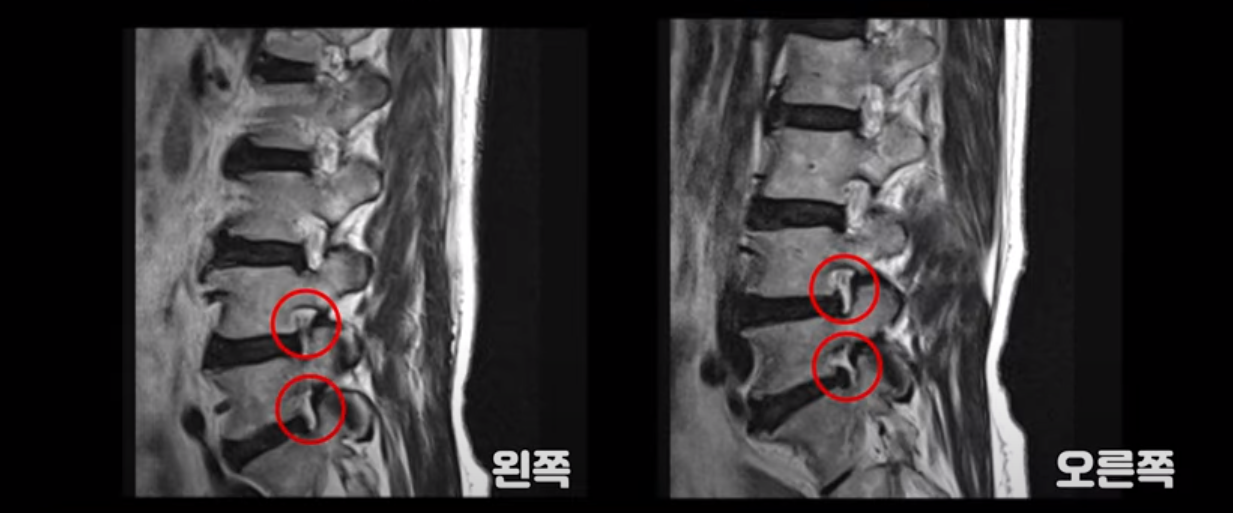

이분 다리는 양쪽이 다 아픈데 양쪽 추공간이 좁아져 있긴 하지만 여전히 하얀 지방이 많이 보이는 상태로 심하게 좁아 보이지는 않습니다.

척추관이 가장 좁아진 4번 5번을 보면 중심성 협착이 있지만 많이 심하지는 않습니다

그런데 저희가 협착증 발병과 치료에 근육이 너무나도 중요하다고 하는 이유는 이렇게 신경 구멍이 심하게 좁아지지 않은 환자도 근육 상태가 안 좋아지면 얼마든지 신경학적 방사통이 생길 수 있기 때문입니다. 이분은 몇 개월 전 아기를 보면서 허리를 무리하게 쓴 후 다리 증상이 시작되었고 그 뒤에 해외 여행 다녀온 이후 증상이 급격히 악화됩니다. 60세 이후 노화와 퇴행으로 신경 구멍들이 조금씩 좁아지고 근육은 줄어들고 약해진 상태에서 무리한 일이나 운동으로 근육의 문제가 심해지면 근육이 허리를 잘 지탱하지 못하니까 신경 눌림 증상이 얼마든지 발생할 수 있습니다. 그런데 심해 보이지 않는 협착도 이 환자분처럼 일단 방사통이 생기고 신경주사가 듣지 않으면 수술하자는 얘기를 듣게 됩니다.